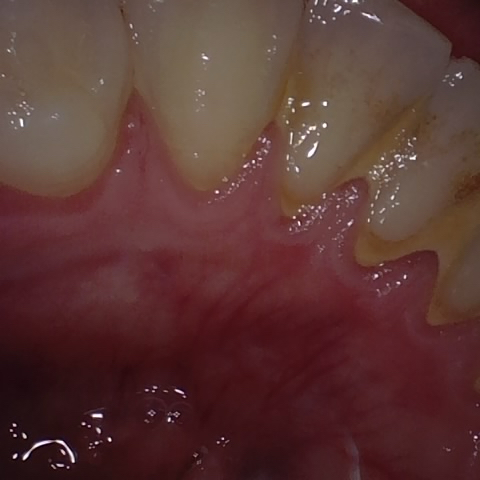

Annotated as "Good"